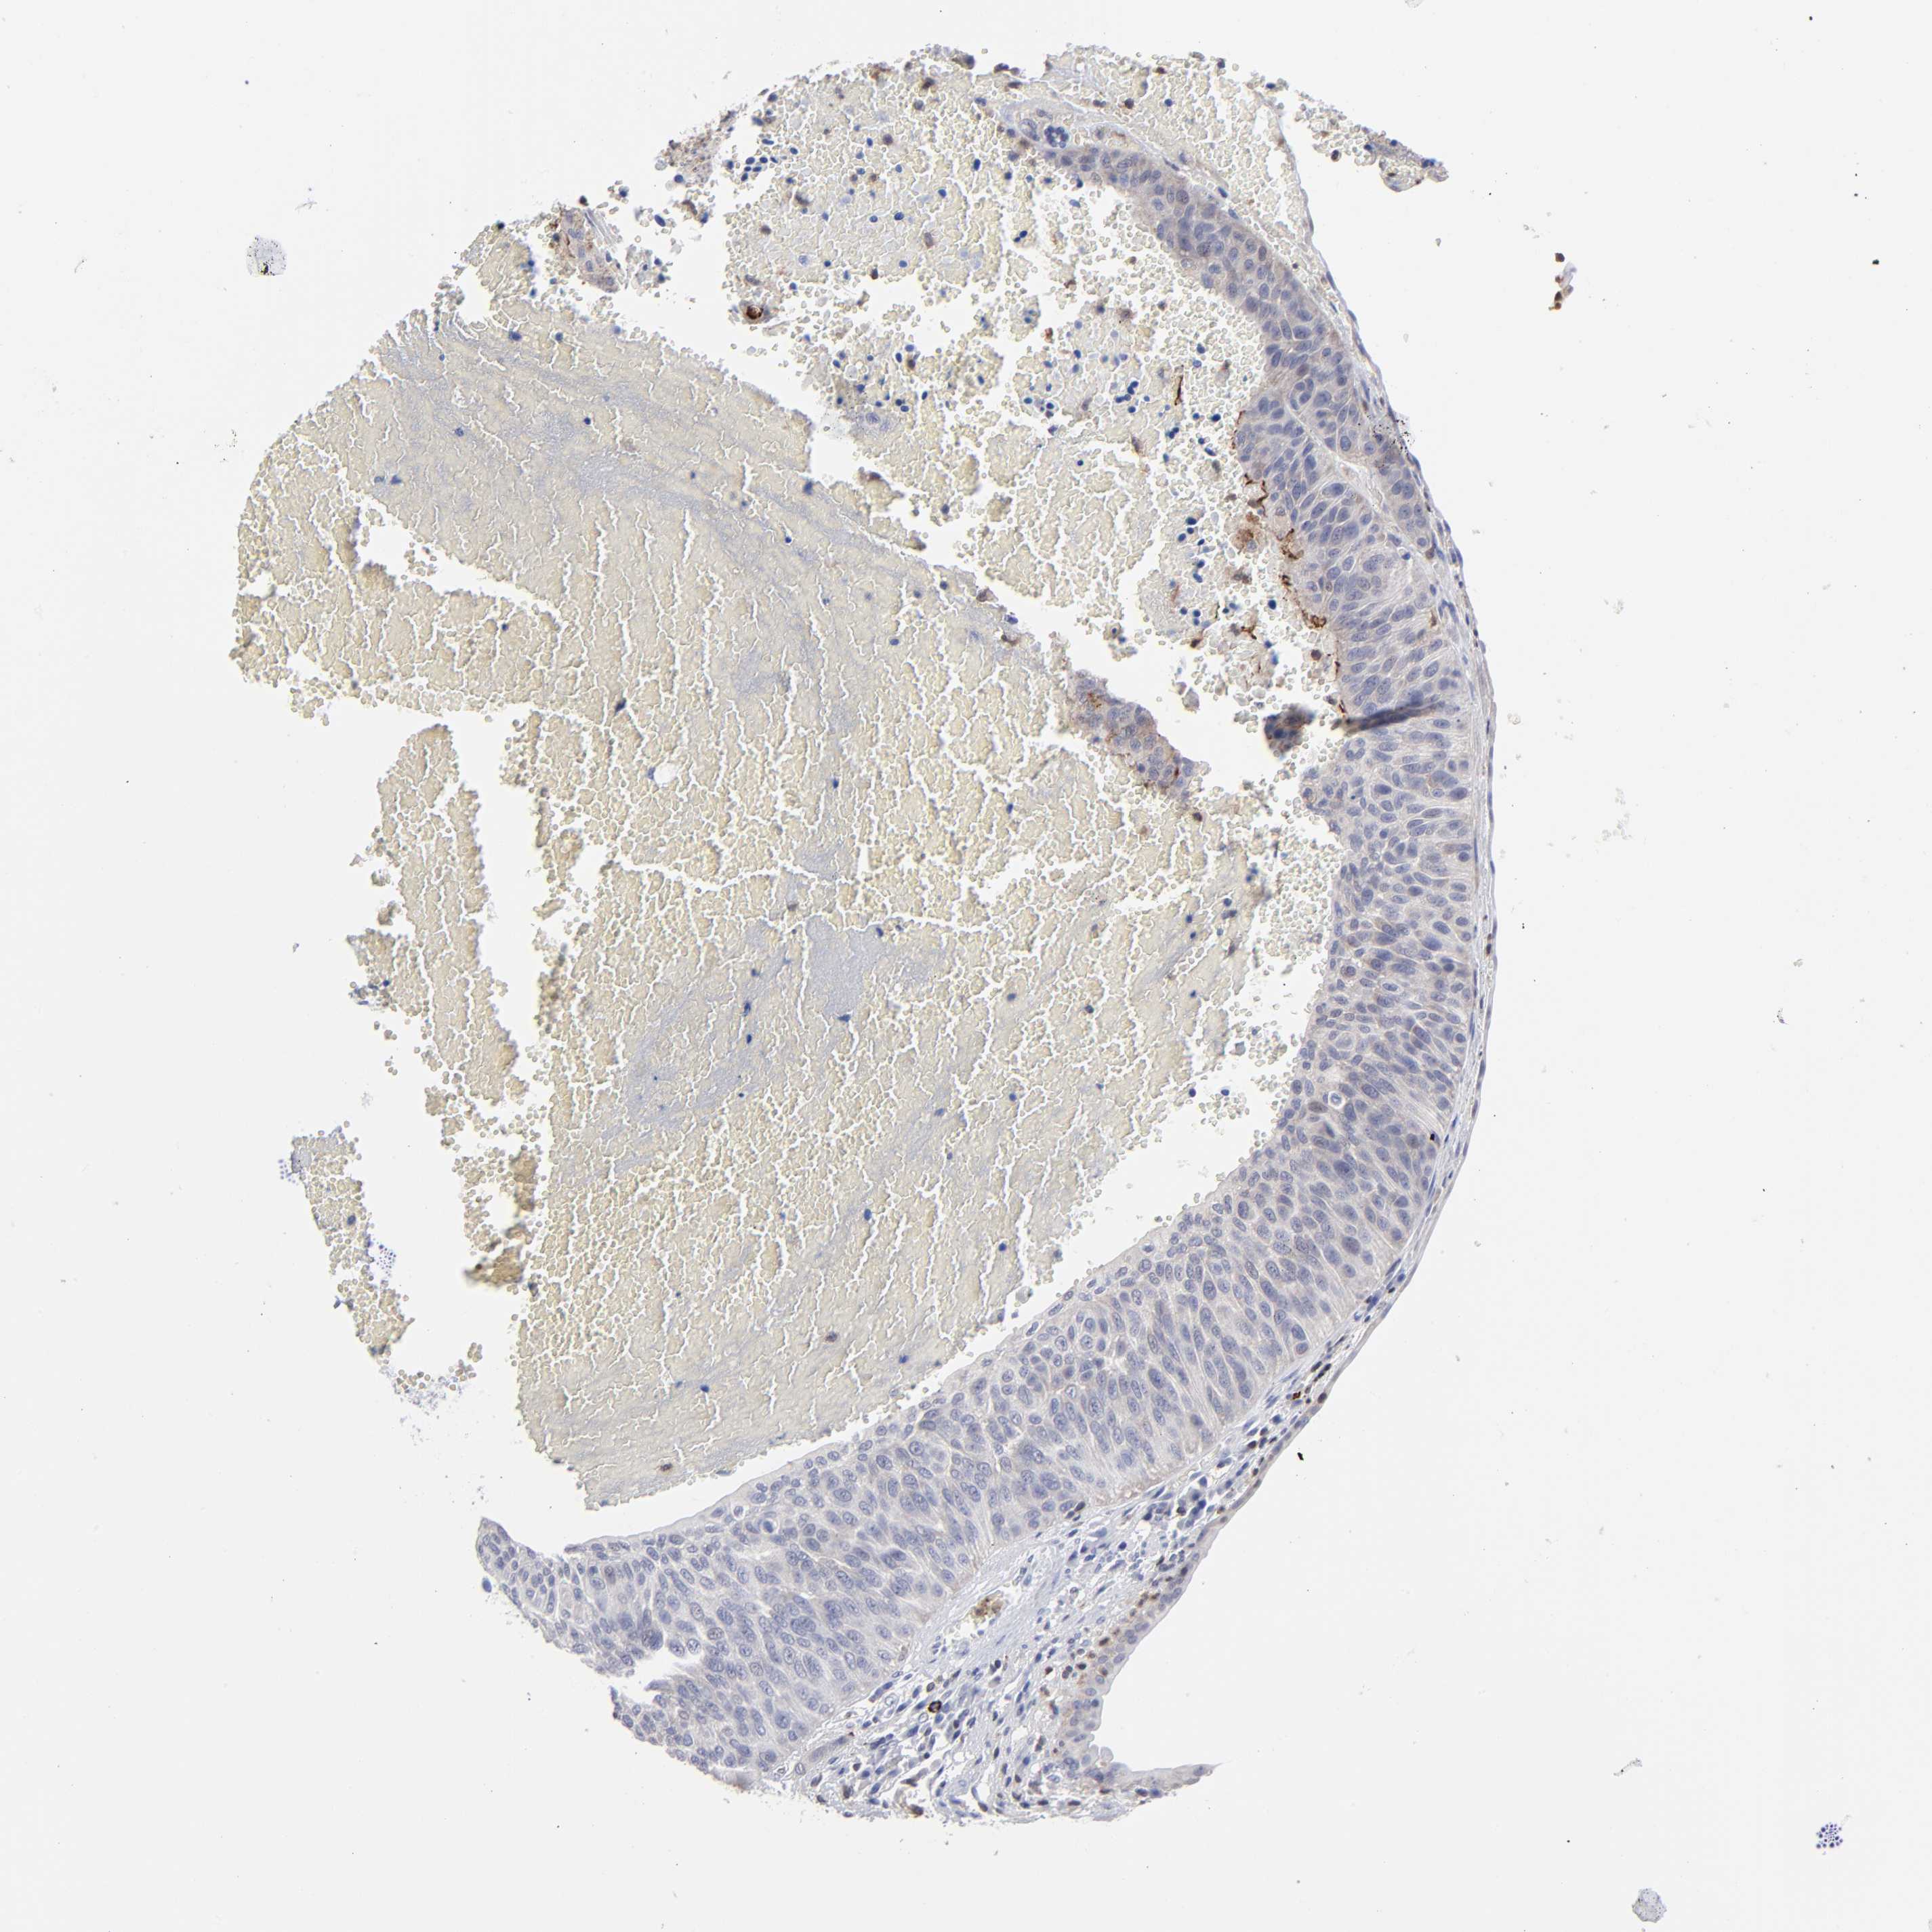

UROTHELIAL CANCER - Protein expressioni

A mouse-over function shows sample information and annotation data. Click on an image to view it in a full screen mode. Samples can be filtered based on level of antibody staining by selecting one or several of the following categories: high, medium, low and not detected. The assay and annotation is described here.

Note that samples used for immunohistochemistry by the Human Protein Atlas do not correspond to samples in the TCGA dataset.

Antibody stainingi

Antibody staining in the annotated cell types in the current human tissue is reported as not detected, low, medium, or high, based on conventional immunohistochemistry profiling in selected tissues. This score is based on the combination of the staining intensity and fraction of stained cells.

Each image is clickable and will lead to virtual microscopy that enables deeper exploration of all samples and also displays staining intensity scores, fraction scores and subcellular localization as well as patient and tissue information for each sample.

Antibody HPA003322

Staining

High

Medium

Low

Not detected

Intensity

Strong

Moderate

Weak

Negative

Quantity

>75%

75%-25%

<25%

None

Location

Nuclear

Cytoplasmic/membranous

Cytoplasmic/membranous,nuclear

Urothelial carcinoma, High grade

Urothelial carcinoma, Low grade